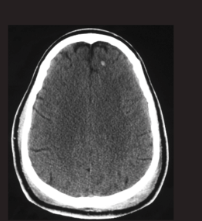

What type of hameotoma is depicted? Epidural haematoma (EDH) Subdural haematoma (SDH) Subarachnoid haematoma (SAH) Intracerebral haematoma (ICH)

What type of hameotoma is depicted? Epidural haematoma (EDH) Subdural haematoma (SDH) **Subarachnoid haematoma (SAH)** Intracerebral haematoma (ICH)

36

What type of hameotoma is depicted? Epidural haematoma (EDH) Subdural haematoma (SDH) **Subarachnoid haematoma (SAH)** Intracerebral haematoma (ICH) There is high-attenuation blood in the Sylvian fissures (blue arrows) and the interhemispheric fissure (red arrow) seen on this non-contrast enhanced CT of the brain. Do not confuse normal, physiologic calcifications (white and black arrows) for bloo